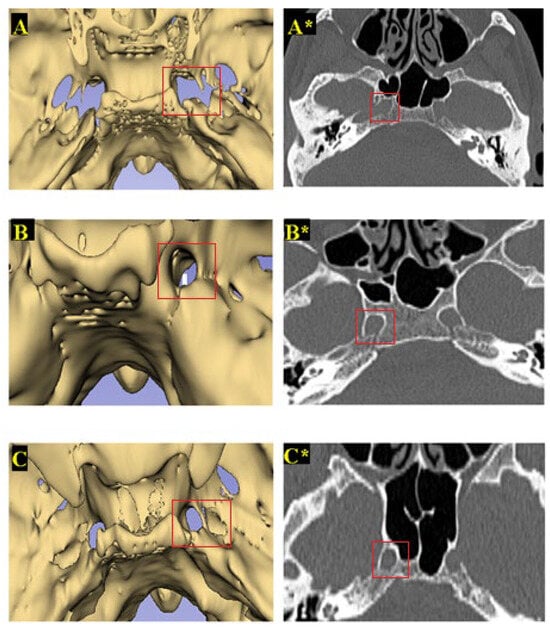

3.2. Classification of FL Types

| FL Types | Total (%/n) | Female (%/n) | Male (%/n) |

|---|---|---|---|

| Right FL | |||

| Type 1 (Normal) | %70.1 (54) | %64.3 (27) | %77.1 (27) |

| Type 2 (Canal-shaped) | %15.6(12) | %26.2 (11) | %2.9 (1) |

| Type 3 (Bridged) | %14.3 (11) | %9.5 (4) | %20.0 (7) |

| Left FL | |||

| Type 1 (Normal) | %72.7 (56) | %73.8 (31) | %71.4 (25) |

| Type 2 (Canal-shaped) | %11.7 (9) | %16.7 (7) | %5.7 (2) |

| Type 3 (Bridged) | %15.6 (12) | %9.5 (4) | %22.9 (8) |